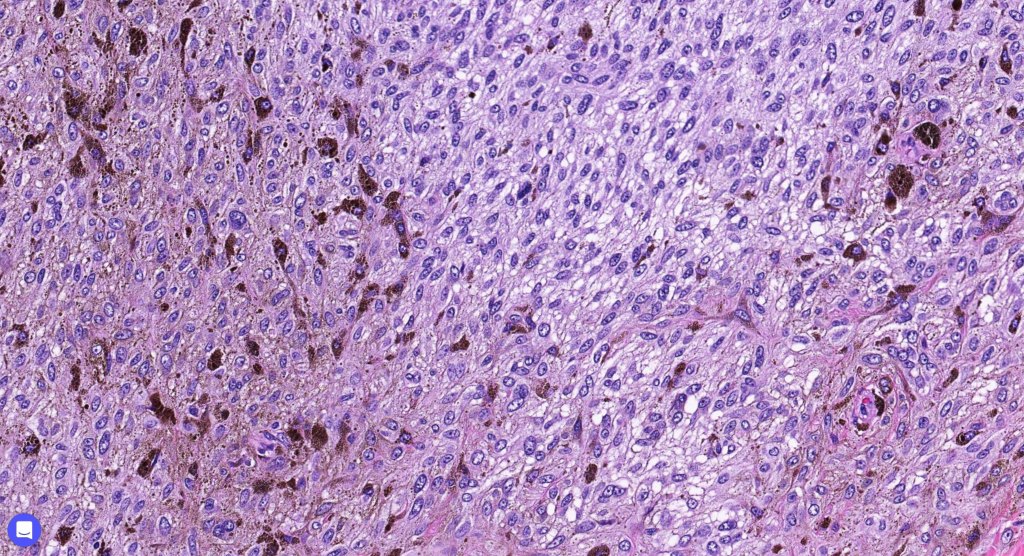

Histologically, it is characterized by a dense population of spindled, dendritic melnanocytes & melanophages with variable fibrosis. It may sometimes represent a component of a combined nevus. Mitotic activity is not usually present and pleomorphism is absent (see atypical blue nevus below). Involvement of the arrector pili muscle is not uncommon.

•Admixture of spindle cells, pigmented bipolar or dendritic cells & melanophages

•Cytoplasm is pale and nuclei are small with inconspicuous nucleoli

•An alveolar pattern is characteristic particularly with clear cell nodules

•Multinucleate giant cells sometimes present

•Stromal fibrosis, myxoid change, vascular hyalinization with cyst formation are often seen

•Balloon cell change